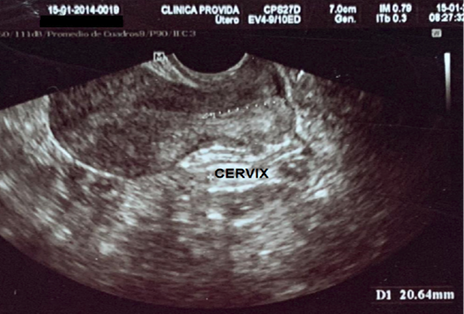

Antecedentes patológicos personales: incompetencia cervical, más aborto recurrente. Se observa la longitud cervical y longitud de útero previo al primer cerclaje en la Figura 1 y 2. Antecedentes quirúrgicos: cerclaje cervical por vía vaginal en la tercera gesta. Antecedentes gineco-obstétricos: menarquia 12 años, ciclos menstruales regulares, duración de 6 días, sangrado moderado. Gestas 4, partos 0, abortos 3, cesáreas 0, hijos vivos 0.

G1: aborto a las 20 semanas de gestación. G2: aborto a las 20 semanas de gestación. G3: aborto a las 21 semanas de gestación a pesar de haberse realizado cerclaje vaginal técnica McDonald a las 12 semanas por el servicio de ginecología-obstetricia del Hospital Básico Provida; se observa en la Figura 3 los hilos del cerclaje con la protrusión de membranas ovulares en vagina el día del aborto. G4: actual, edad gestacional 13 semanas por fecha de ultima menstruación (FUM).